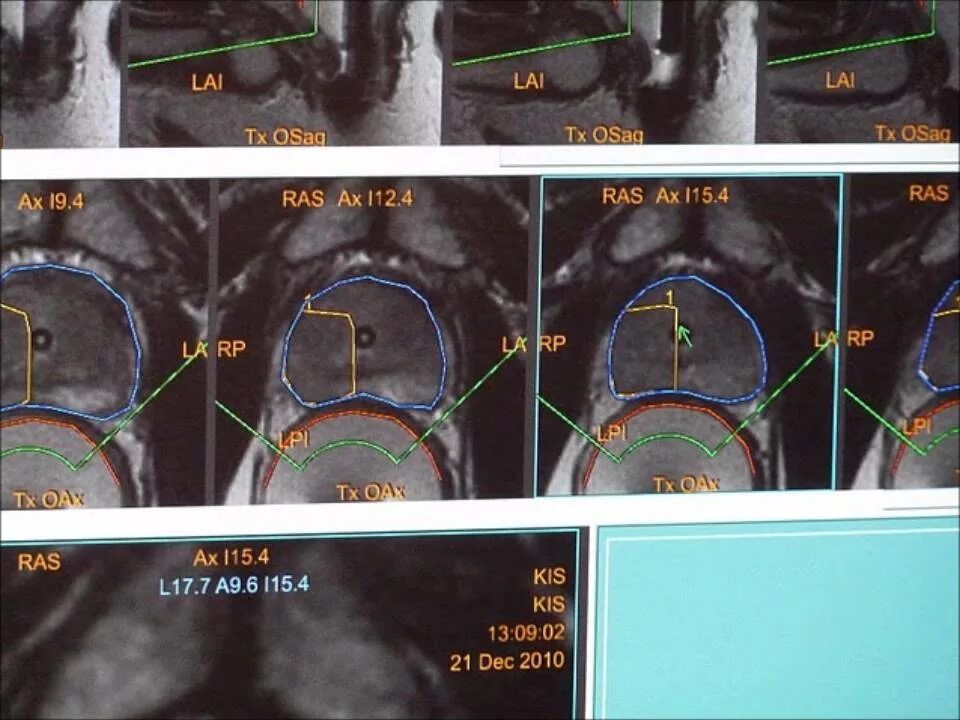

Абляция миомы